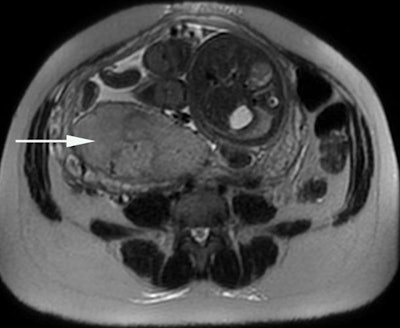

Placental oxygenation can be assessed by the blood oxygen level-dependent (BOLD) MRI technique, using T2* mapping (below) and combining a morphological analysis (above). The placenta is localized posteriorly on the right (arrow). The T2* value within each pixel is encoded with a color scale. Images courtesy of Prof. Nathalie Siauve.

Placental oxygenation can be assessed by the blood oxygen level-dependent (BOLD) MRI technique, using T2* mapping (below) and combining a morphological analysis (above). The placenta is localized posteriorly on the right (arrow). The T2* value within each pixel is encoded with a color scale. Images courtesy of Prof. Nathalie Siauve."This organ plays a regulatory role extending well beyond nutrition and respiration, also encompassing the endocrine and immune system regulations," Siauve pointed out. "As a signaling organ, the placenta produces a myriad of bioactive molecules affecting both maternal and fetal metabolisms and physiologies."